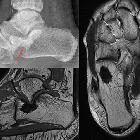

Osteosarkom des Kalkaneus

Radiographic features

Although plain radiography can provide a lot of information, MRI is used for local staging by assessing intraosseous tumor extension (e.g. growth plate/epiphysis, skip lesions) and soft-tissue involvement. Chest CT and bone scanning have a role in distant staging.

MRI

MRI is proving an essential tool to determine accurate local staging and assessment for limb-sparing resection, particularly for evaluation of intraosseous tumor extension and soft-tissue involvement. Evaluation of the growth plate is also essential as up to 75-88% of metaphyseal tumors do cross the growth plate into the epiphysis .